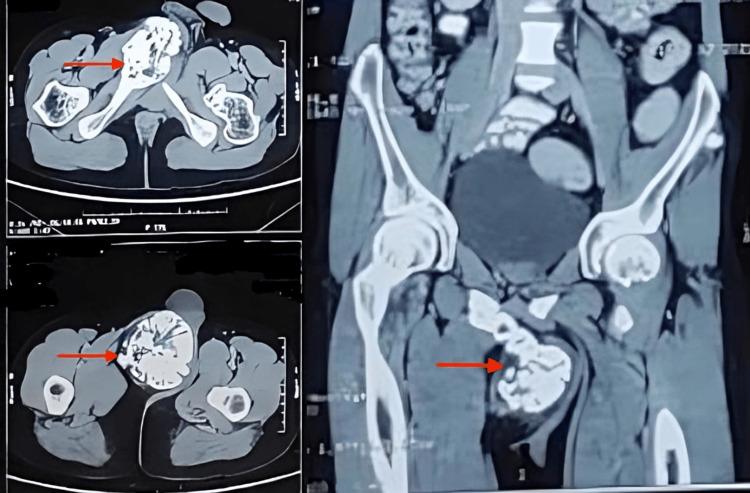

Osteochondromas are the most common benign bone tumours, which usually manifest as bony projections covered with a cartilaginous cap and originate from the metaphysis of long bones. However, they can create discomfort and difficulties, particularly in non-traditional places, although they are frequently asymptomatic. An osteochondroma arising from the right inferior pubic ramus is a rare case. A 31-year-old gentleman presented with an enlarged swelling in the right groin for 17 years, giving him great discomfort, difficulty in performing sexual activities, irritation, and aesthetic issues. The swelling was insidious in onset, firm and non-pliable, measuring 15 x 11 cm, and gradually progressive over the years. It displaced the scrotum and was fixed to the underlying bone. This pedunculated bone growth arising from the right inferior pubic ramus was identified by plain X-ray, pelvic anteroposterior and lateral view, and computed tomography imaging. An excisional biopsy was performed on the patient using the femoribus internus perineal approach. The tumour was carefully removed piecemeal using an osteotome. After surgery, radiographs confirmed complete removal. This case study demonstrates the effective application of the femoribus internus perineal approach and excision technique. There was a resolution of symptoms, and no symptom recurrence was noted after surgery. This case illustrates the importance of tailored surgical methods for managing osteochondromas in non-traditional locations.

骨软骨瘤是最常见的良性骨肿瘤,通常表现为覆盖有软骨帽的骨性突起,起源于长骨的干骺端。然而,尽管它们常常无症状,但也可能引起不适和困难,尤其是在非传统部位。起源于右耻骨下支的骨软骨瘤是一种罕见病例。一名31岁男性因右腹股沟区肿物增大17年就诊,该肿物给他带来极大不适,导致性行为困难、刺激感以及美观问题。肿物起病隐匿,质地硬且不可压缩,大小为15×11厘米,多年来逐渐增大。它使阴囊移位并与下方骨骼固定。通过骨盆前后位和侧位平片以及计算机断层扫描成像,确定了这个起源于右耻骨下支的带蒂骨生长物。采用经股内侧会阴入路对患者进行了切除活检。使用骨凿小心地将肿瘤逐块切除。术后X线片证实肿瘤已完全切除。本病例研究展示了经股内侧会阴入路和切除技术的有效应用。症状得到缓解,术后未观察到症状复发。该病例说明了针对非传统部位骨软骨瘤采用定制手术方法的重要性。